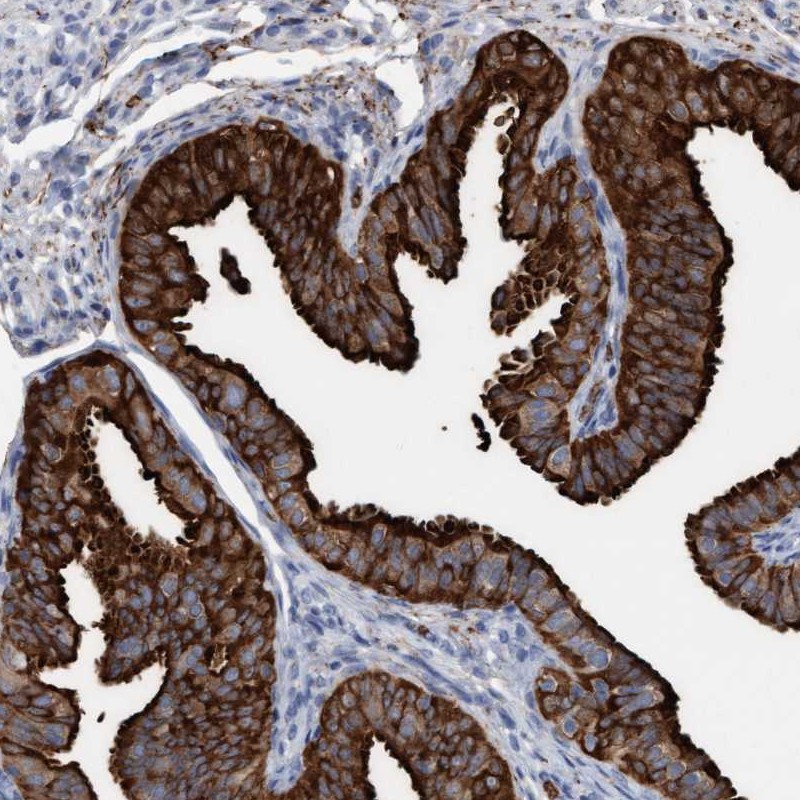

Immunohistochemical staining of human fallopian tube shows strong cytoplasmic and membranous positivity in glandular cells.